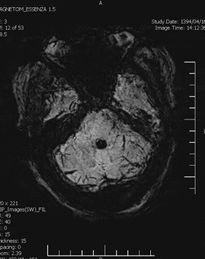

Background: Cavernous hemangiomas are common benign vascular malformations. Their existence in the intraventricular region is very rare. Case Reports: A 43-year old woman with an occipital headache was admitted to the emergency ward. Brain computed tomography scan showed mild hydrocephalus and multiple intraventricular isodense lesions. Imaging findings, especially of Gradient Resonance Echo imaging, were in favor of multiple intraventricular cavernous malformations. Conclusion: This is a rare presentation of multiple cavernous malformation as occipital headache without needing surgical intervention in this phase. Coexistence of periventricular plaques like Radiologically isolated syndrome of Multiple sclerosis is another unique aspect in this report. [GMJ.2017;6(1):61-65]